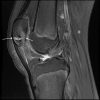

Xương bánh chè 2 mảnh

» Thông tin: Nam giới – 14 tuổi.

» Lâm sàng: Đau khớp gối.